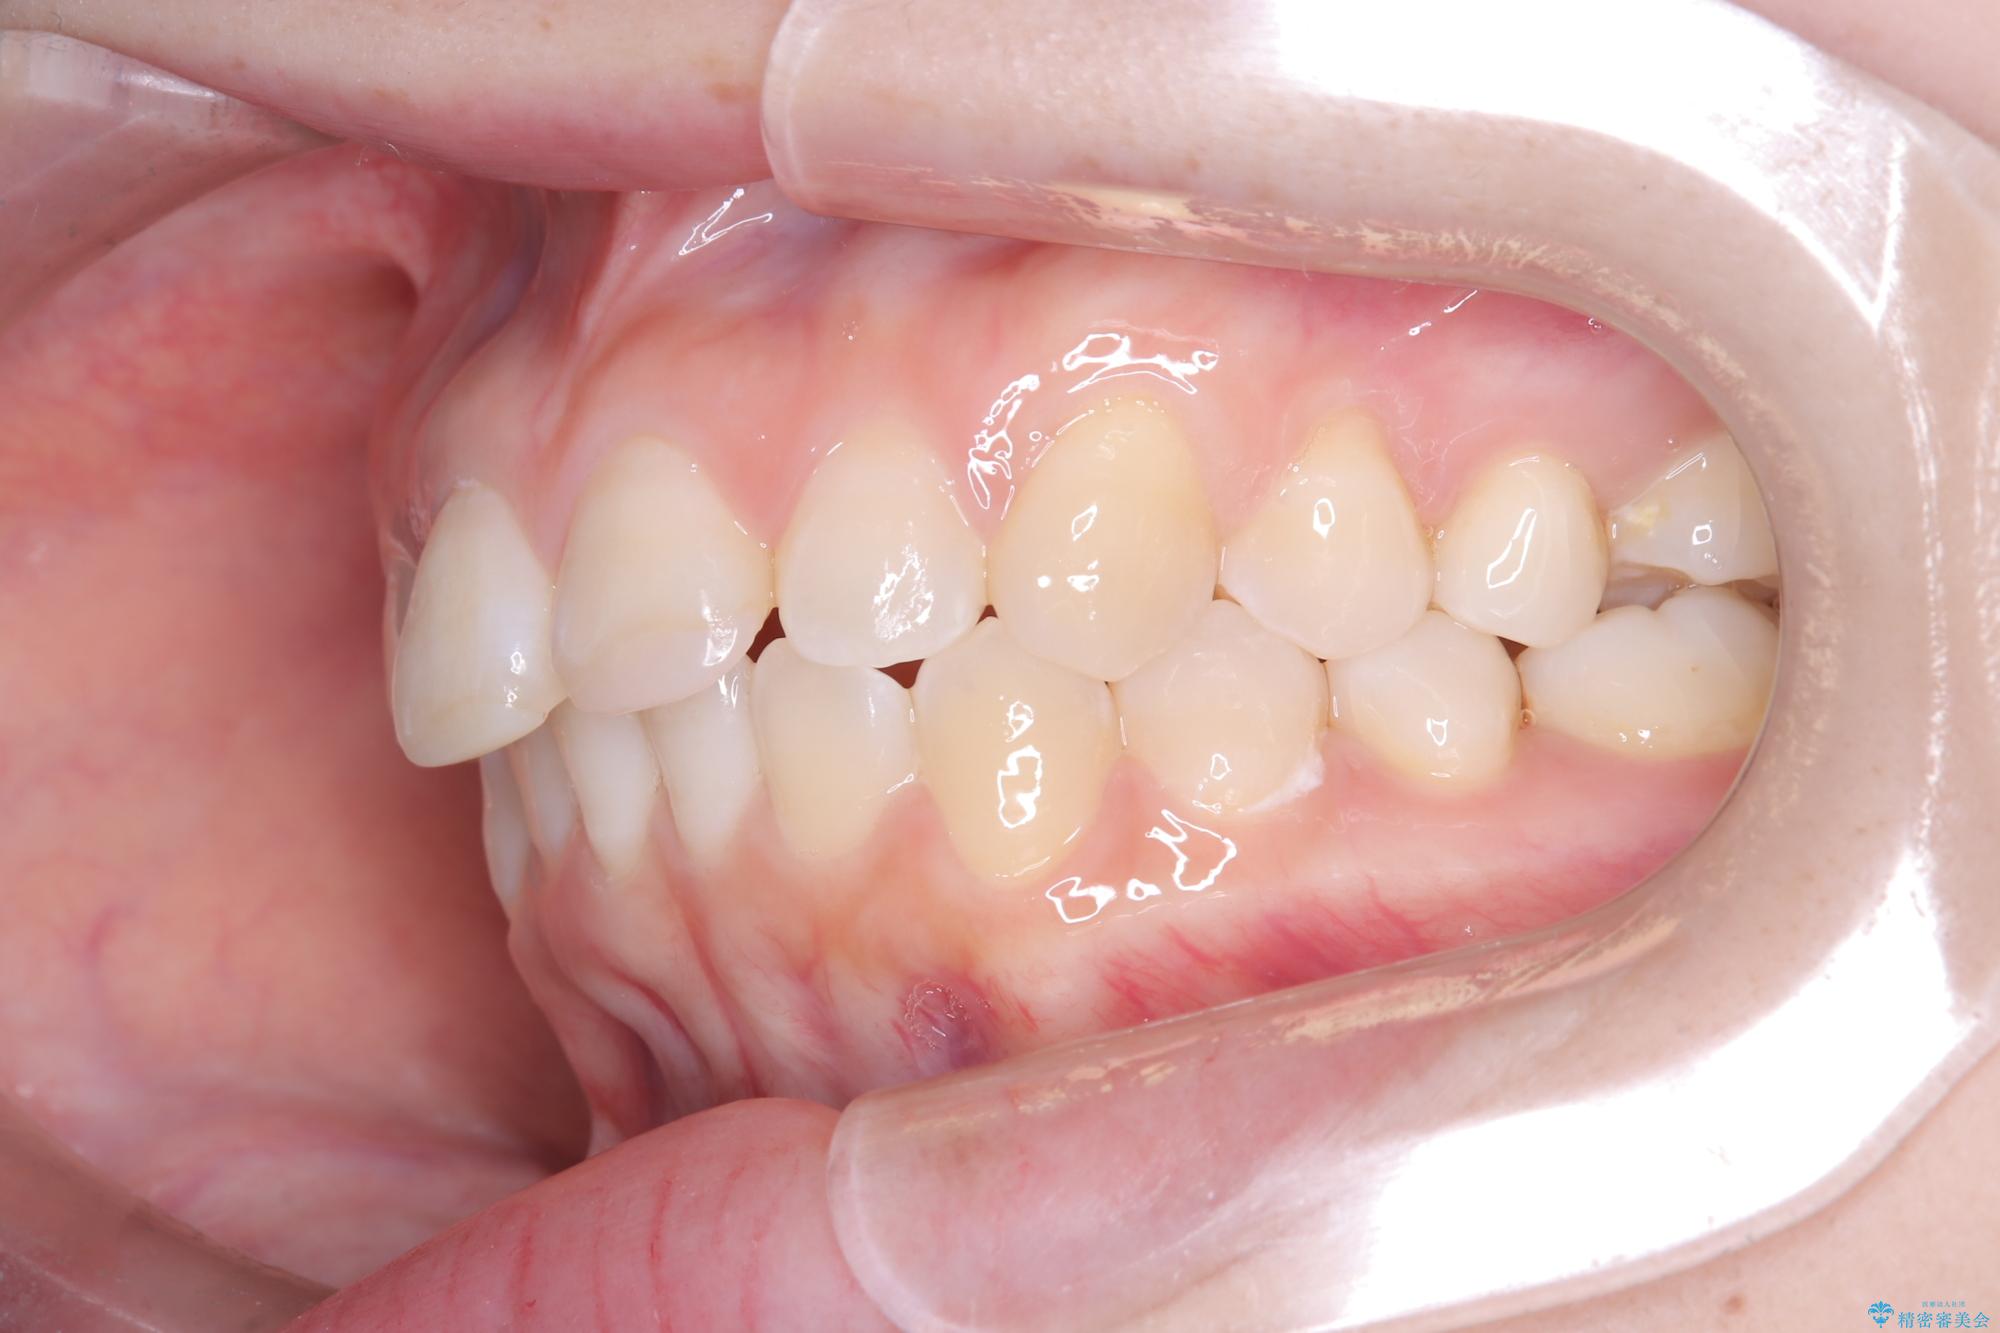

- 前歯のデコボコ(叢生)を気にされてご来院されました。精密な検査の結果、歯が並ぶスペースが不足していることが判明。患者様のご希望から、透明で目立ちにくいインビザライン(マウスピース矯正)による治療計画を立案しました。抜歯を避け、奥歯全体を奥へ動かす遠心移動という方法でスペースを確保し、前歯の叢生を解消することを目指します。

今回の矯正治療では、透明なマウスピース型の装置インビザラインを使用しました。この装置は取り外し可能で、日常生活で目立ちません。治療は、緻密に計算された計画に基づき、段階的に作製されたマウスピースを交換していくことで、奥歯から順に全体を後方へ移動させる遠心移動を実施。これにより、前歯を並べるための十分なスペースが確保され、デコボコが解消されました。抜歯することなく、機能的にも審美的にも整った美しい歯並びを獲得していただけました。